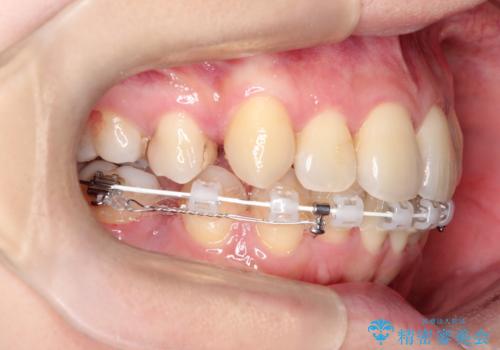

ガタガタの抜歯矯正を裏側ワイヤーを使っての目立たない矯正

- ハーフリンガル

- 八重歯とガタガタを主訴に来院されました。

目立たないワイヤー矯正を希望されたので、上下左右のはを1本ずつ抜歯して、ハーフリンガル(上顎だけ裏側)にて矯正をすることにしました。